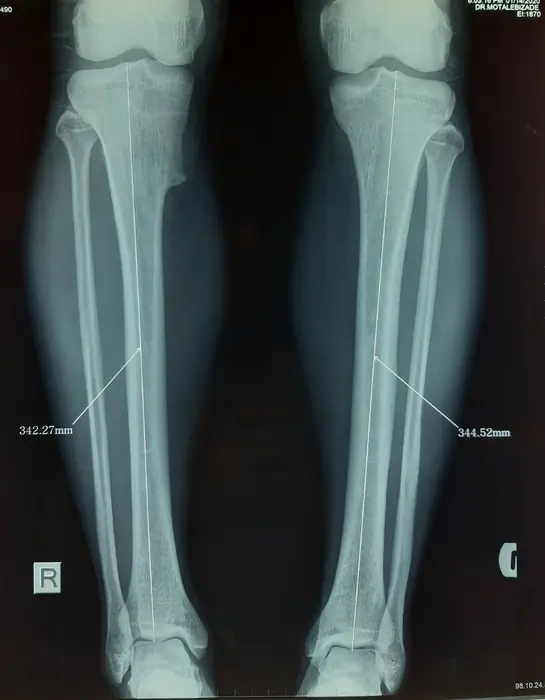

نمونه رادیولوژی افزایش قد ساق با روش MTN (بیمار ۲۰ ساله آقا)

در این تصاویر روند افزایش قد ساق با میله تلسکوپی MTN در یک بیمار ۲۰ ساله را میبینید. در رادیوگرافی قبل از عمل، طول هر دو تیبیا در محدوده ۳۴۳ میلیمتر اندازهگیری شده است. پس از جراحی، میله تلسکوپی MTN داخل هر دو ساق قرار گرفته و استخوان در ناحیه میانی برش داده شده است.